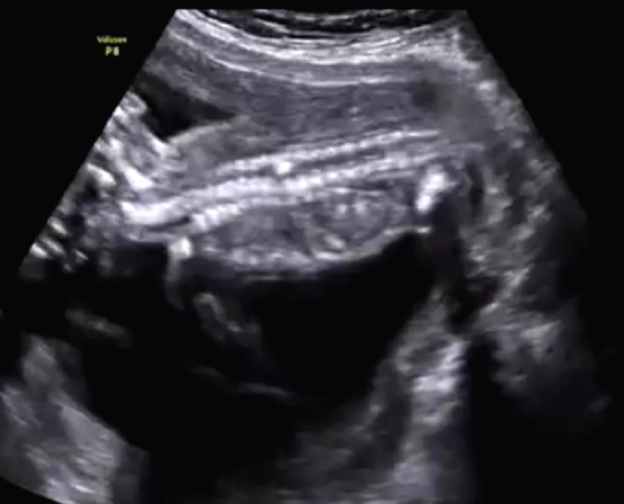

Figure 3. Third view of coronal section of the fetal spine. (Image courtesy of Firoz Bhuvar, MD)

Imaging studies: This routine transabdominal obstetric sonography was performed to exclude any congenital fetal anomalies. The patient had not undergone any sonographic study prior to this scan. The images seen in Figure 1, Figure 2, and Figure 3 show the coronal section of the fetal spine and were taken during this routine sonographic examination.

In Figures 1, 2, and 3, the volume of amniotic fluid appears normal. The fetal abdomen also shows no significant abnormality. The placenta is fundic and posterior. No retroplacental hematoma is seen.

The most prominent anatomy in these images is the fetal spine. The fetal head is to the left of the images, and the fetal lower limbs are to the right of the images. The upper cervical and thoracic spines appear normal. However, there is an abnormality within the lower thoracic vertebrae that appears as an echogenic lesion within the spinal canal. It looks linear and extends within the mid-portion of the spinal canal. We cannot further distinguish the abnormality in this region. What are the diagnostic possibilities based on these images, at this stage?

After studying the aforementioned images, there is no obvious herniation of the meninges through a dorsal or ventral defect in the spine. However, there is an obvious anomaly visible in the images of the axial section of thoracic vertebrae, which was also visible in the images of the coronal section of the thoracic vertebrae. The anomaly is some form of division of the spinal canal.

True diplomyelia is characterized by near-total division of the spinal cord, which is not the case here. The division is localized to the affected lower thoracic spines. In addition, there is a vertical echogenic, possibly bony, septum within the affected thoracic vertebrae. This finding suggests the possibility of diastematomyelia. This condition is seen as a partial or complete bony septum or fibrous septum that divides the spinal canal (localized to affected spine), with partial division of the spinal cord in the affected parts only.